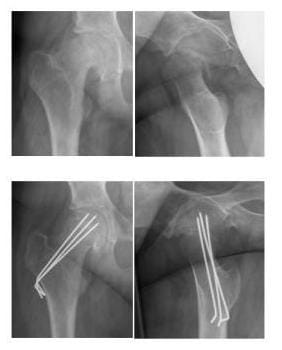

In der Pubertät finden natürliche Veränderungen in der Wachstumsfuge zwischen dem Hüftkopf und dem  Schenkelhals statt. In einigen Fällen kann die Fuge aber so gelockert sein, dass der Hüftkopf abrutscht. Diese Wachstumsfugenlösung nennt man Epiphyseolysis capitis femoris (ECF). Sie kann schleichend stattfinden oder sich akut ereignen. Die Kinder geben dann Schmerzen in der Hüfte oder dem Knie an und wollen nicht mehr laufen. Das Abrutschen kann auch die Durchblutung des Hüftkopfes gefährden. Die Behandlung soll daher das weitere Abrutschen des Hüftkopfes verhindern und eine Fehlstellung ggf. wieder korrigieren. Hierzu wird der Hüftkopf mit einer Schraube oder Drähten gesichert. Eine geringe Fehlstellung des Hüftkopfes kann toleriert werden. Ist der Hüftkopf aber sehr stark verschoben, muss er wieder eingerichtet werden. Manchmal ist auch eine spätere Korrektur der Fehlstellung sinnvoll. Regelmäßige Kontrollen sind bei jedem Patienten auch nach der Operation bis zum Wachstumsabschluss erforderlich. Bei starkem Wachstum müssen Schrauben oder Drähte ggf. auch einmal gewechselt werden. Nach Wachstumsabschluss ist die Fuge verknöchert und das eingebrachte Material kann wieder entfernt werden.

EPIPHYSEOLYSIS CAPITIS FEMORIS

Die Bilder zeigen den abgerutschten Hüftkopf aus 2 Perspektiven und zeigen das Ergebnis nach Einrichtung und Sicherung mit Drähten

Die oberen Bilder zeigen den abgerutschten Hüftkopf aus 2 Perspektiven, die unteren Bilder zeigen das Ergebnis nach Einrichtung und Sicherung mit Drähten. (Bilder: Orthopädie)